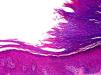

HistopathologyThe histopathology findings of the lesions have been practically identical in all patients. There is a depression of the epidermis caused by a reduction in the thickness of the corneal layer, with borders that are very well-defined. The transition between the normal and the affected epidermis is abrupt, with a marked step from the normal corneal layer, which is usually thick on the palms and soles, to the thin corneal layer of the lesion (Fig. 3). The thinning of the corneal layer is typically associated with slight thinning of the granular layer, causing the hypokeratosis to lie over an area of hypogranulosis. However, the corneocytes in the lesion show normal keratinization, giving rise to an orthokeratotic corneal layer with a multilayered structure and basophilic coloration, and the underlying keratinocytes show no noticeable morphological abnormalities.

In some cases the corneocytes at the transition between the normal corneal layer of the adjacent healthy skin and the thinned corneal layer of the lesion have a smooth and more eosinophilic appearance than the corneocytes immediately adjacent to the lesion (Fig. 4). Serial sections of the lesion stained with periodic acid-Schiff have revealed no signs of parakeratosis or cornoid lamella, which constitute the fundamental histopathological criteria for excluding porokeratosis, nor has it been possible to demonstrate continuity of alterations between the step in the epidermis and any of the underlying intraepidermal structures. Furthermore, the acrosyringia within the lesion are also involved in the alterations, as the corneal layer covering acrosyringia in the area of the lesion is not as thick as the corneal layer covering these structures in the adjacent healthy skin. In the lesions located in the thenar region of the palm, the underlying papillary dermis shows a degree of elastosis that varies between patients, but associated inflammatory infiltrates are not usually observed. It would therefore appear that the erythematous color of the lesions is because the atrophy of the corneal layer leads to greater transparency of the affected epidermis, and the greater proximity of the dermal vessels is what causes the erythema.